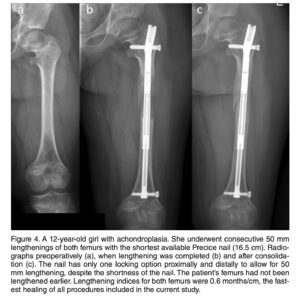

Sob a coordenação do Dr. Marcelo Pigatto D’Amado, membro da Sociedade Brasileira de Ortopedia e Traumatologia e da AO Foundation, o CBOT é pioneiro no uso de hastes intramedulares motorizadas (PRECICE, FITBONE) para alongamento ósseo no Brasil.